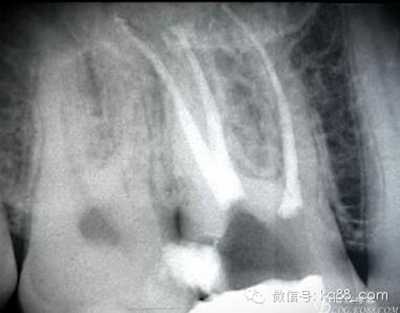

1.jpg

根管治療后X片